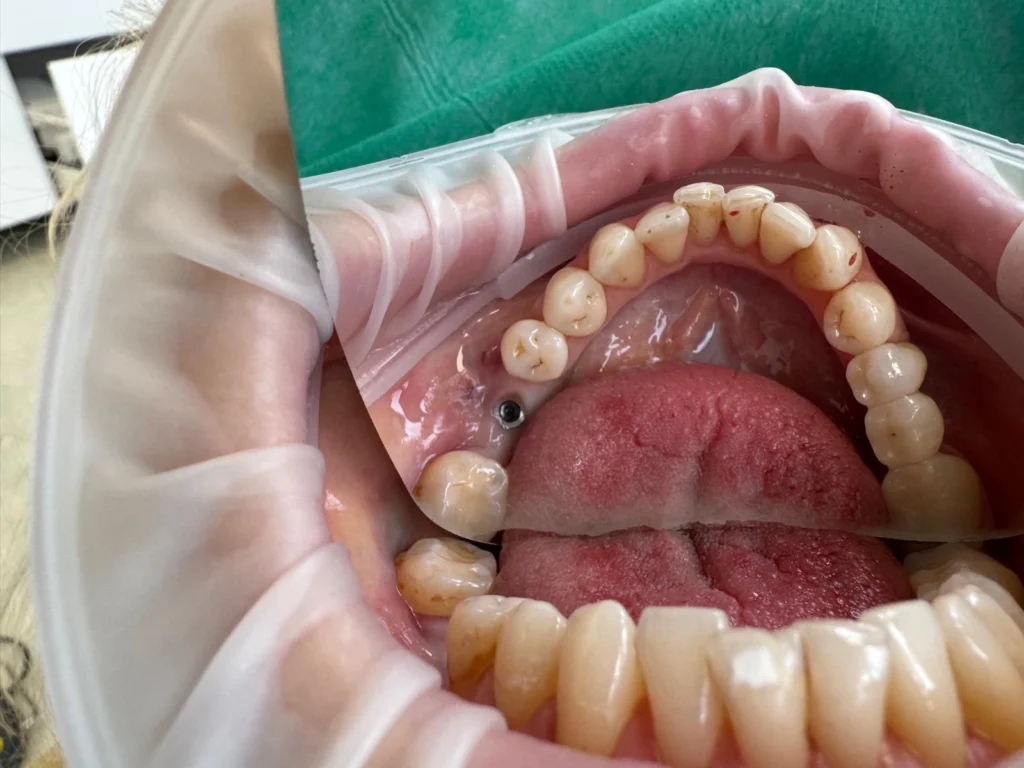

poza pivot implant dentar

Implant dentar înainte de coroană

Un implant dentar este o soluție modernă pentru înlocuirea unui dinte lipsă, fără a afecta dinții vecini. El constă într-un șurub din titan (sau zirconiu) care se integrează în osul maxilar, acționând ca o „rădăcină” artificială, peste care se montează o coroană dentară estetică.